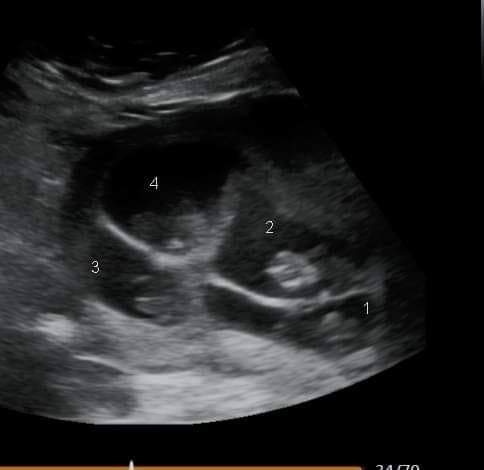

Tháng 12/2021, y tá nhi khoa 34 tuổi đến từ Phelps, New York, cô Karissa Vancamp-Smith, và chồng cô, anh Dillon, 32 tuổi phát hiện rằng cô Vancamp-Smith đang mang thai. Sau khi trải qua ba lần sẩy thai và mất một con khi còn sơ sinh, họ vô cùng chấn động khi bác sỹ siêu âm tiết lộ rằng cô Vancamp-Smith đang mang thai bốn trong một buổi siêu âm riêng tư ở tuần thứ 6.

“Ngay lập tức, hai em bé xuất hiện trên màn hình, và sau đó một em bé thứ ba đến, và rồi em bé thứ tư,” cô nói. “Chúng tôi không thốt nên lời.”

“Chúng tôi không biết các con là sinh cùng trứng cho đến khi bác sĩ nhận thấy sự giống nhau của chúng và chỉ có một nhau thai. Các con vẫn khỏe mạnh nhưng cần ở lại bệnh viện do sinh non.”